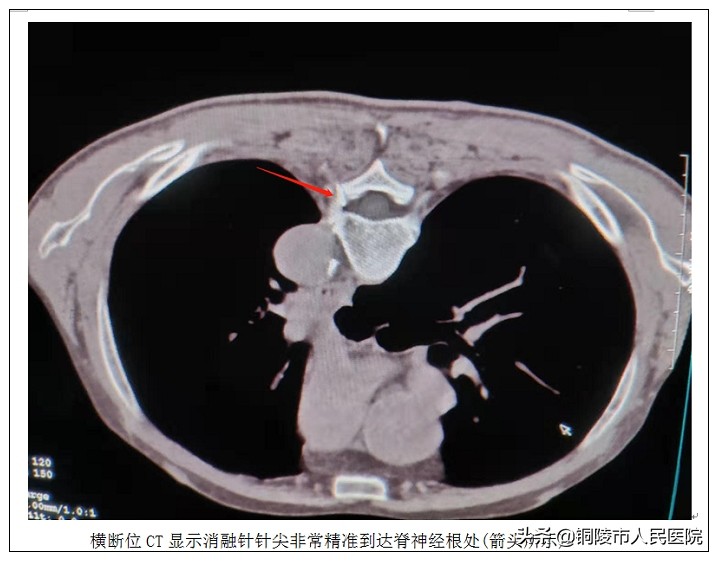

接受治疗的是一名78岁老年男性,确诊为带状疱疹后遗神经痛收住神经内科。该患者2月前患有带状疱疹,皮肤带状疱疹痊愈后,左侧胸背部及前胸部疱疹部位出现电击样阵发性疼痛,经口服药物治疗后,仍遗留较重疼痛,穿衣翻身受限,严重影响睡眠,可谓苦不堪言。经我院影像中心介入治疗团队会诊后,10月10日,介入治疗团队在CT引导下为患者实施了精准的脊神经射频温控热凝术治疗。整个手术仅用时40分钟,术后患者疼痛程度明显减轻,穿衣翻身动作轻松完成,夜间睡眠良好,生活质量大幅提高。